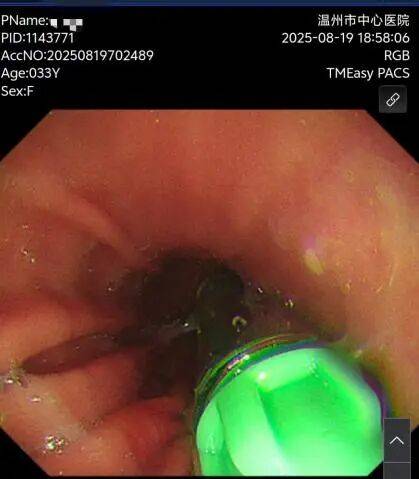

而我在11月25日的时候来取出放置的胃流转支架术,手术过程也是非常的顺利,没有丝毫的痛,等麻醉过后我已经是躺在病床上挂点滴了。

从8月18号支架置入时候的95KG到11月25日取出支架时候的83KG,共减了12KG。以前买的衣服和裤子都在慢慢的变大,我的体重也在慢慢的减轻,在这3个月里,我慢慢的养成了一个健康的进食习惯,少量多餐,不吃高热量的食品,多喝水,不吃夜宵,所以胃流转支架非常适合我这种不爱运动的宅家的懒人!非常感谢这项新技术,我又可以穿更好看的衣服,也越来越自信。